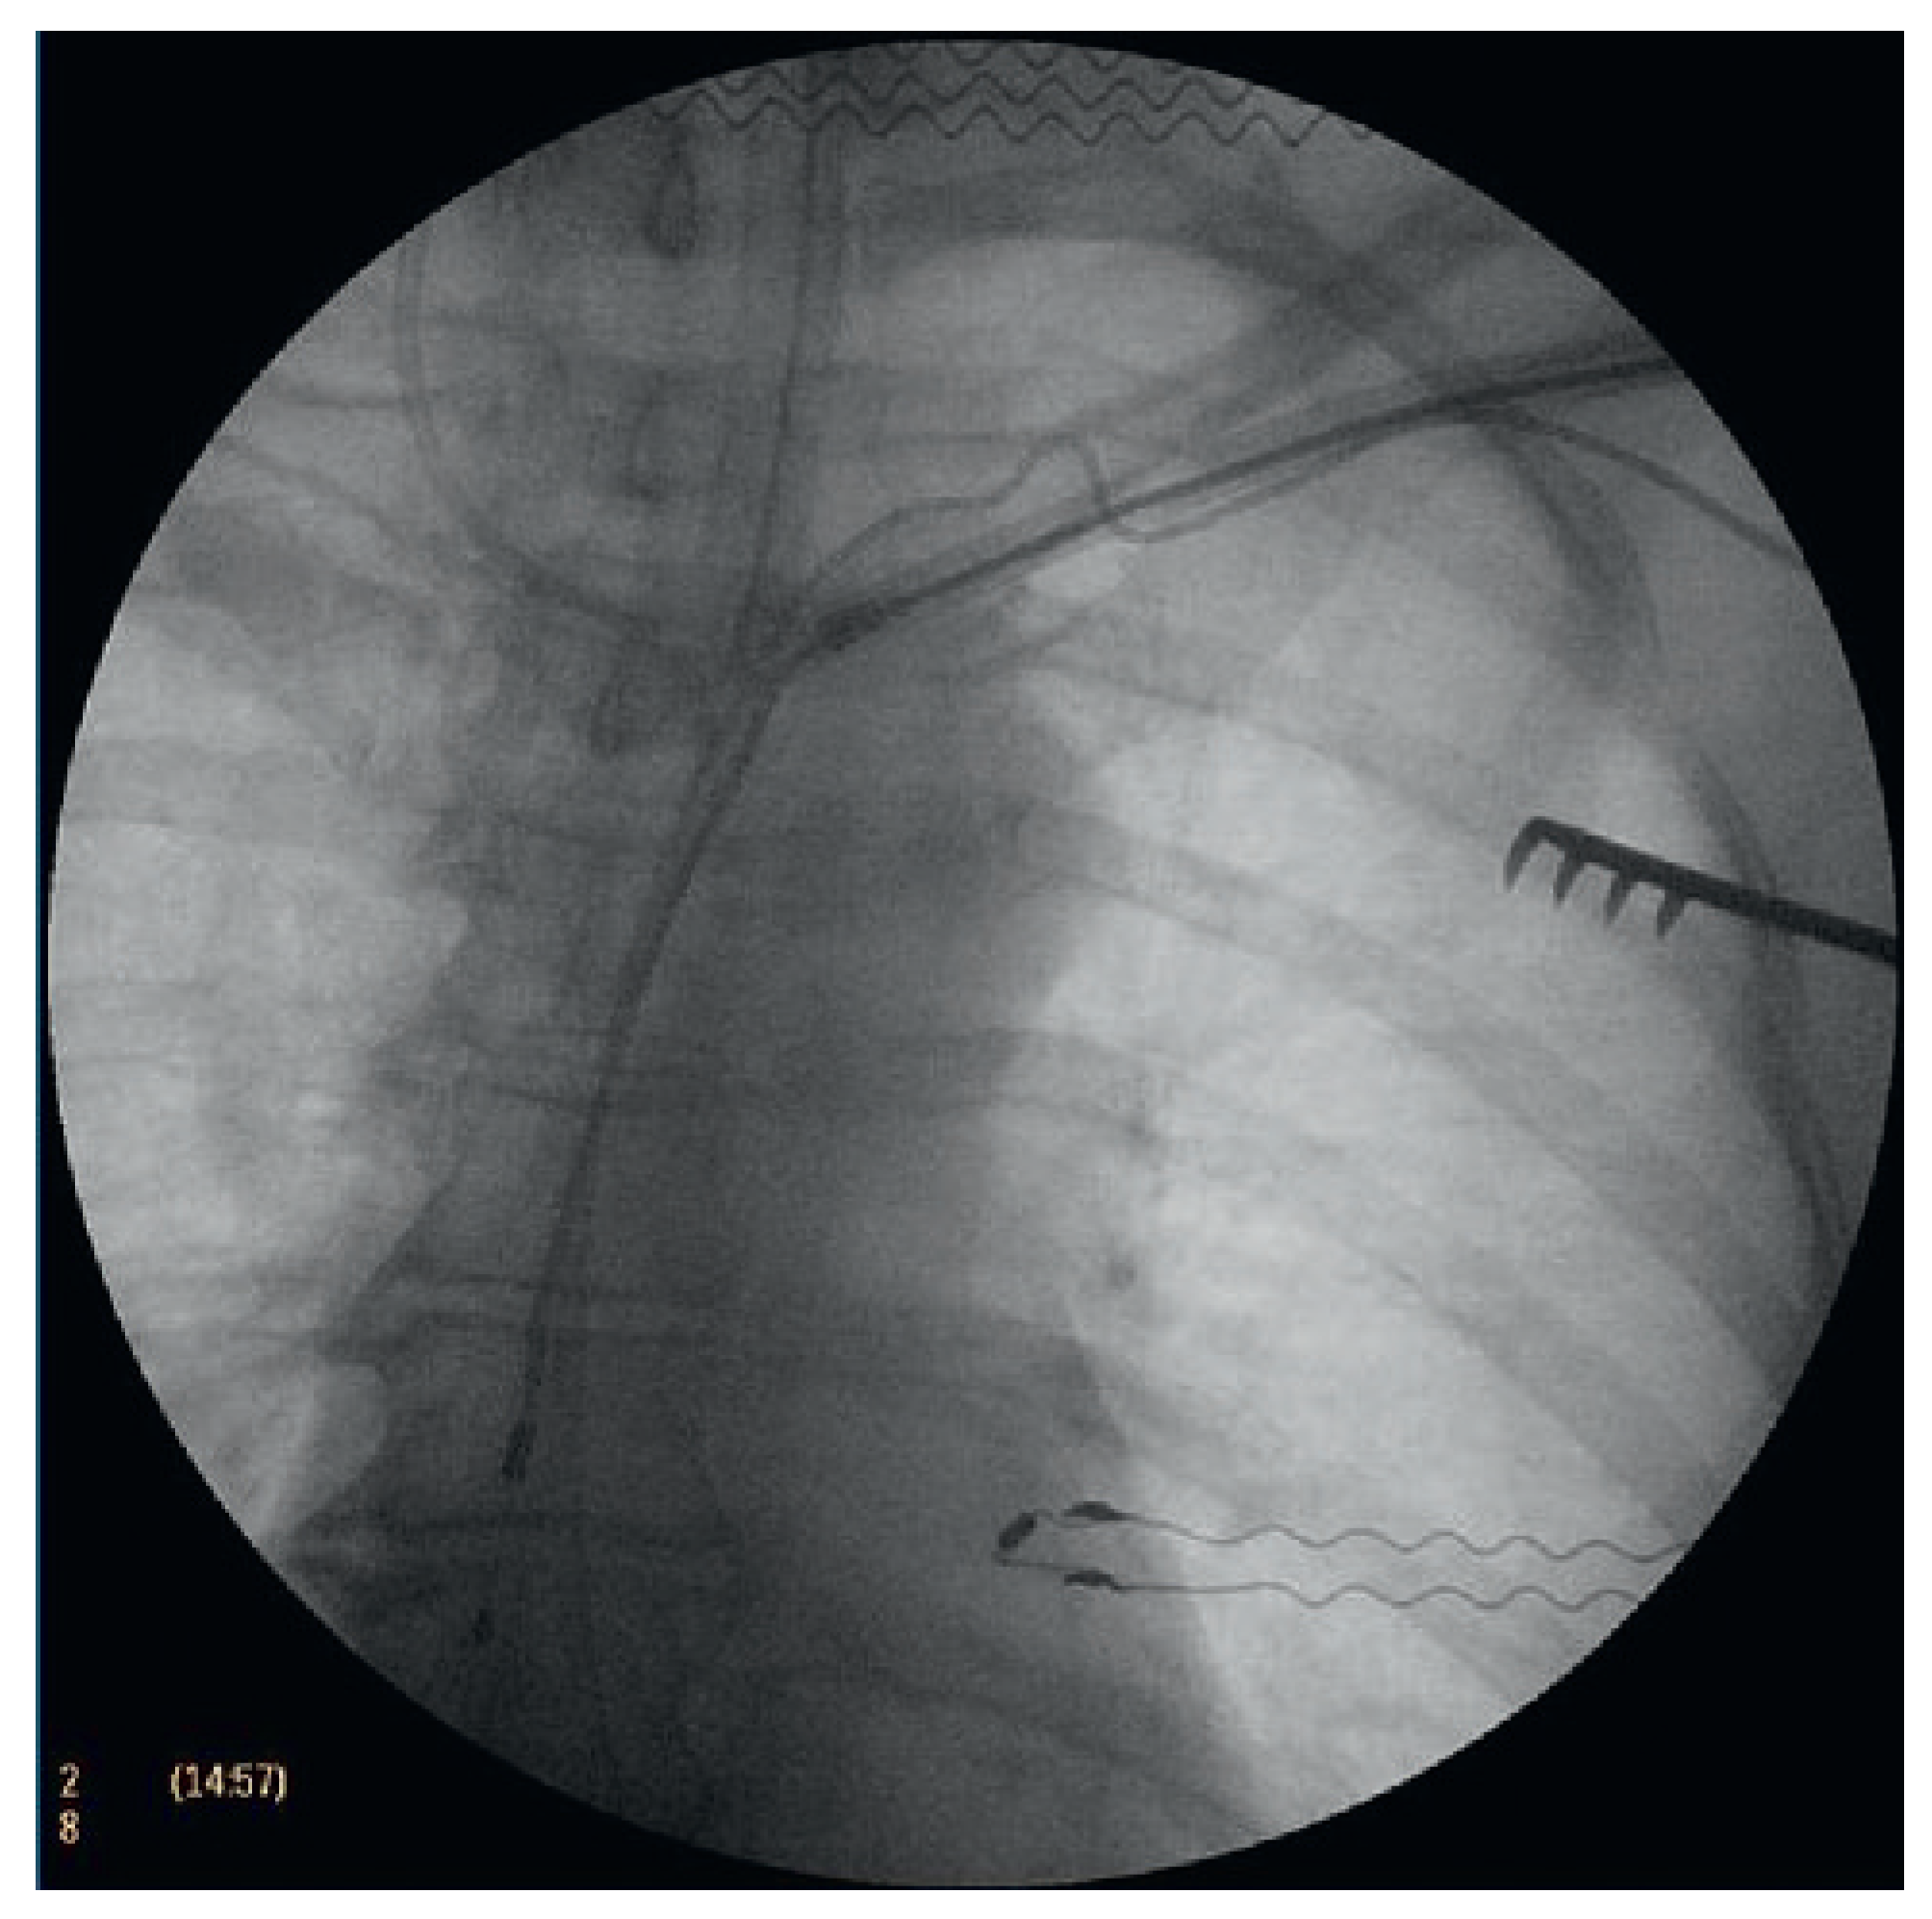

Welche Verfahren bzw. Tools kommen zur Anwendung?